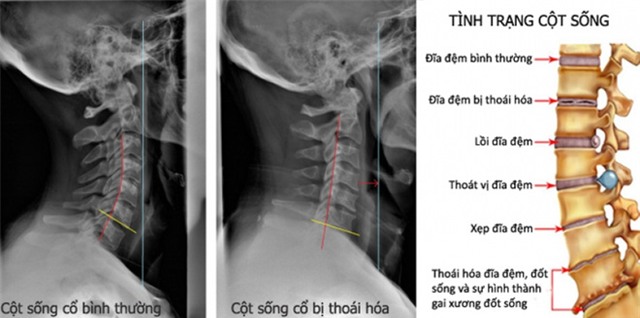

Đây là hiện tượng thoái hóa đốt sống cổ, tổn thương nặng vùng cơ trên phần cổ, cần phải lập tức điều trị phục hồi chức năng, trị liệu nhanh để hồi phục công năng hoạt động của cổ.

Theo bác sĩ Hồ Tiểu Quân, trẻ em trong một thời gian dài ngồi yên một chỗ để chơi iPad, điện thoại di động sẽ gây ra đau cơ cổ, căng thẳng, co thắt dây chằng, nếu không can thiệp, nguy cơ trong tương lai sẽ bị thoát vị đĩa đệm cổ và các bệnh khác.

Hiện tượng này cũng xảy ra phổ biến và lứa tuổi ngày càng nhỏ. Không những thế, thoái hóa đốt sống cổ ở trẻ em còn gây nguy hiểm lớn hơn rất nhiều so với người lớn, và thiệt hại đối với cuộc sống của trẻ là không hề nhỏ.

Ngoài ra, xương của trẻ em đang trong giai đoạn phát triển, căn bệnh này có thể ảnh hưởng đến kích thước của đốt sống cổ, phát triển dị dạng, trường hợp nghiêm trọng thậm chí có thể ảnh hưởng đến ngực, thắt lưng và các phần xương khác, thậm chí làm hạn chế phát triển chiều cao.

Khi trẻ em chơi trò chơi, chúng sẽ ngồi yên "bất động" và giữ tư thế đó trong một thời gian dài. Lâu và thường xuyên như vậy, cổ sẽ cúi gập xuống gây võng xương.

Cách ngồi như vậy có tác hại tĩnh, không nhìn thấy ngay lập tức, trẻ sẽ cảm thấy đau từ từ mỗi hôm một ít, cộng với ban đêm ngủ trong phòng điều hòa lạnh, đặc biệt dễ bị tổn thương dẫn đến cứng cổ.